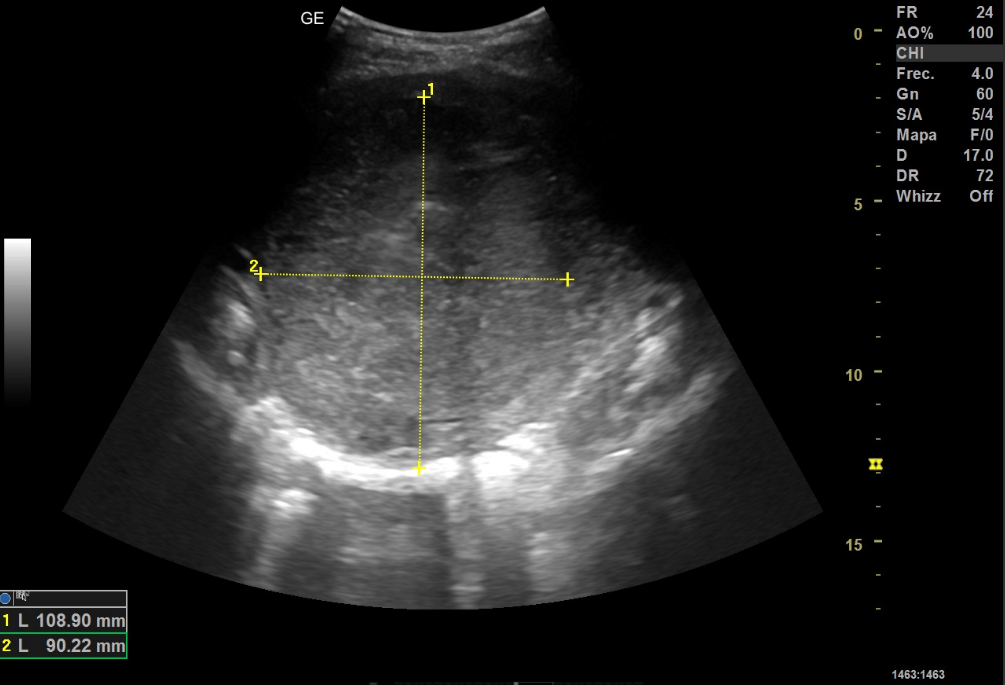

Se le realiza a la paciente ecografía abdominal con sonda cónvex, donde se objetiva en la zona anteriormente mencionada masa de unos 138 mm en su eje longitudinal y 108x90 mm en un corte transversal, no pudiendo precisar con exactitud el origen de la misma. Al aplicar el Doppler color se observa una captación periférica.